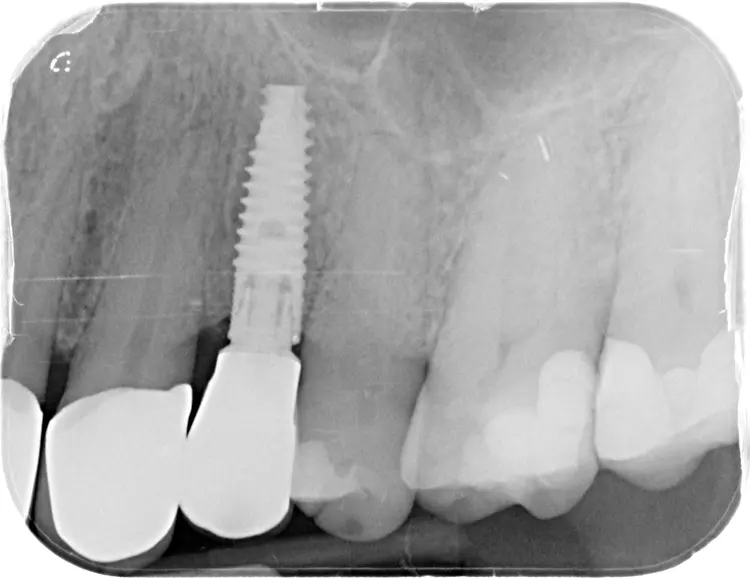

Neuversorgung Oberkieferfront auf Altimplantat 21

Die 49-jährige Patientin beklagte die ungleiche Höhe der Schneidekanten an den Kronen 11 und 21. In diesem Zusammenhang wurde das Gesamterscheinungsbild analysiert und entschieden, die Zähne 13-23 zu überkronen und dabei die Altkronen an 11 und an dem Implantat 21 zu erneuern. Die verschachtelt stehenden Zähne im Unterkiefer sollen im Nachgang per Aligner-Therapie ausgerichtet werden.

Dabei wurde die beabsichtigte Situation im Vorab per Wax-up simuliert. Beim Entfernen der Altkrone 21 wurde ersichtlich, dass ein Titanabutment eingesetzt wurde, an dem sich Konkremente und Zementreste befanden, die zu einer marginalen Mukositis am Implantat führten.